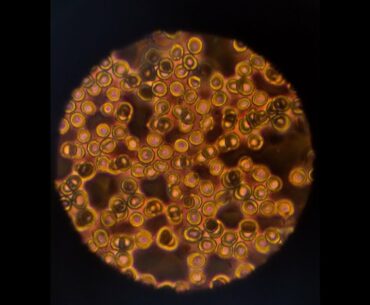

A huge new study shows vitamin supplements have essentially no ability to prevent cancer or cardiovascular disease. Click here to subscribe: https://www.youtube.com/c/methodsmanmd?sub_confirmation=1 Get more medical news analysis at https://www.methodsman.com or https://www.medscape.com #vitamins #cancer #heartdisease